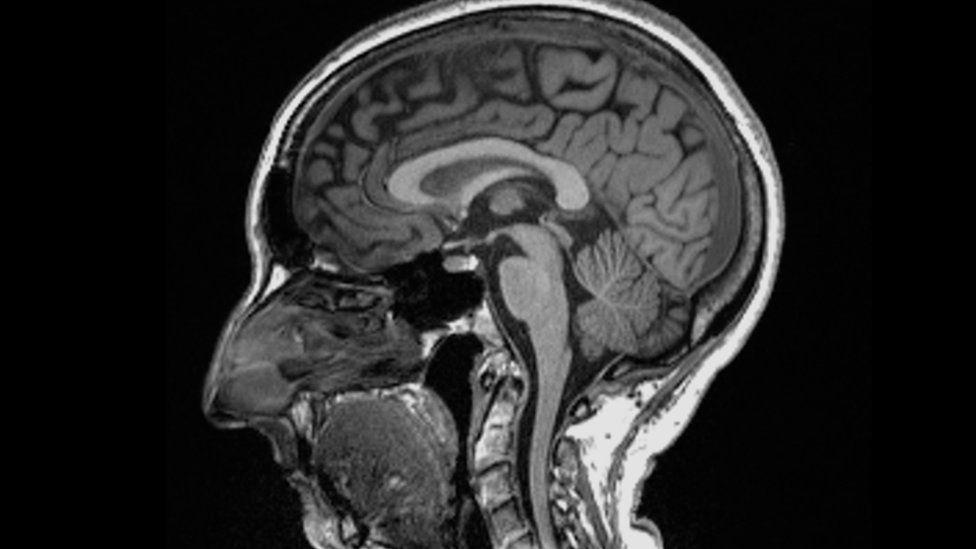

Africa-Press – Mauritius. Catching Covid may cause changes to the brain, a study suggests. Scientists found significant differences in MRI (magnetic resonance imaging) scans before and after infection.

Even after a mild infection, the overall size of the brain had shrunk slightly, with less grey matter in the parts related to smell and memory. The researchers do not know whether the changes are permanent but stressed the brain could heal. The study is published in the journal Nature.

They found: The overall brain size in infected participants had shrunk between 0.2 and 2% There were losses in grey matter in the olfactory areas, linked to smell, and regions linked to memory

The most significant loss of grey matter was in the olfactory areas – but it is unclear whether the virus directly attacks this region or cells simply die off through lack of use after people with Covid lose their sense of smell.